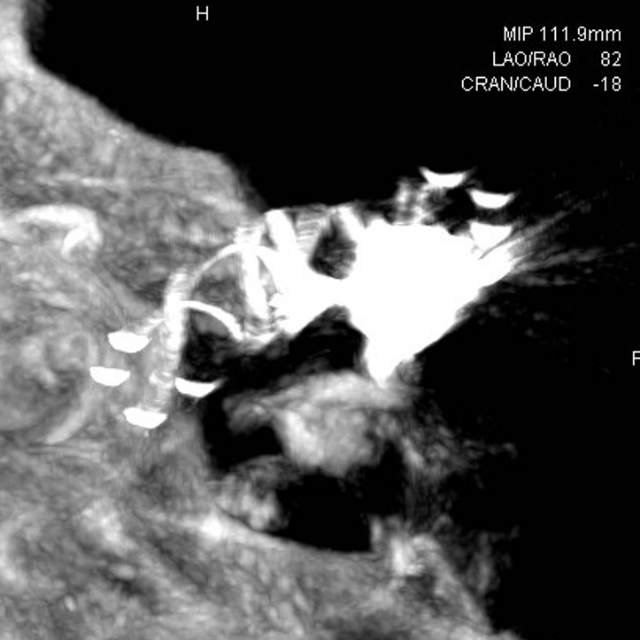

术中评估:动脉瘤位于后交通段的位置,靠近颈内动脉分叉部,颈内动脉交通段的长度相对短小,而且呈现喇叭口的形态,支架不容易锚定,容易出现跳跃“”嗑瓜子”现象。如果支架超过分叉部,覆盖大脑前动脉的起始部,可能会造成后续的大脑前动脉的血管变细。

手术难点:支架远端超过分叉部,操作简单;支架远端若紧邻分叉部近段,操做要求高。

手术过程:术中采用“一个支架+一个弹簧圈”的简约模式顺利结束手术,消除了动脉瘤破裂出血的风险。

手术结果:本次手术具有“创伤小、花费少、时间短、出院快”的特点,而且支架紧邻分叉部近段,没有覆盖大脑前动脉、支架打开贴壁良好、所有分支保持通畅~~~